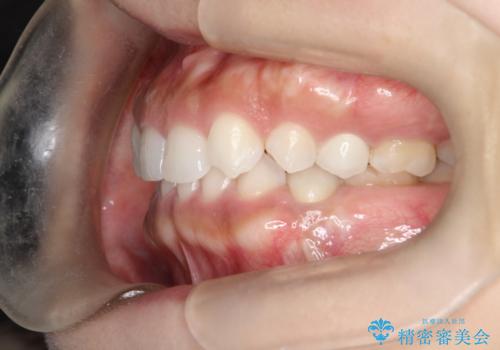

- 後続永久歯が欠損した患者様です。

矯正治療にて歯並びを改善したのち、インプラントにて咬合回復を行う治療計画としました。

捻転が強い部分だけはワイヤーの部分矯正で対応しております。